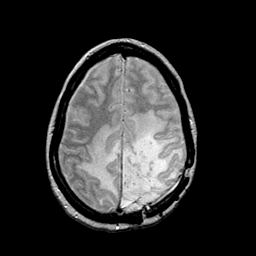

MR Study #2 -- Slice #38